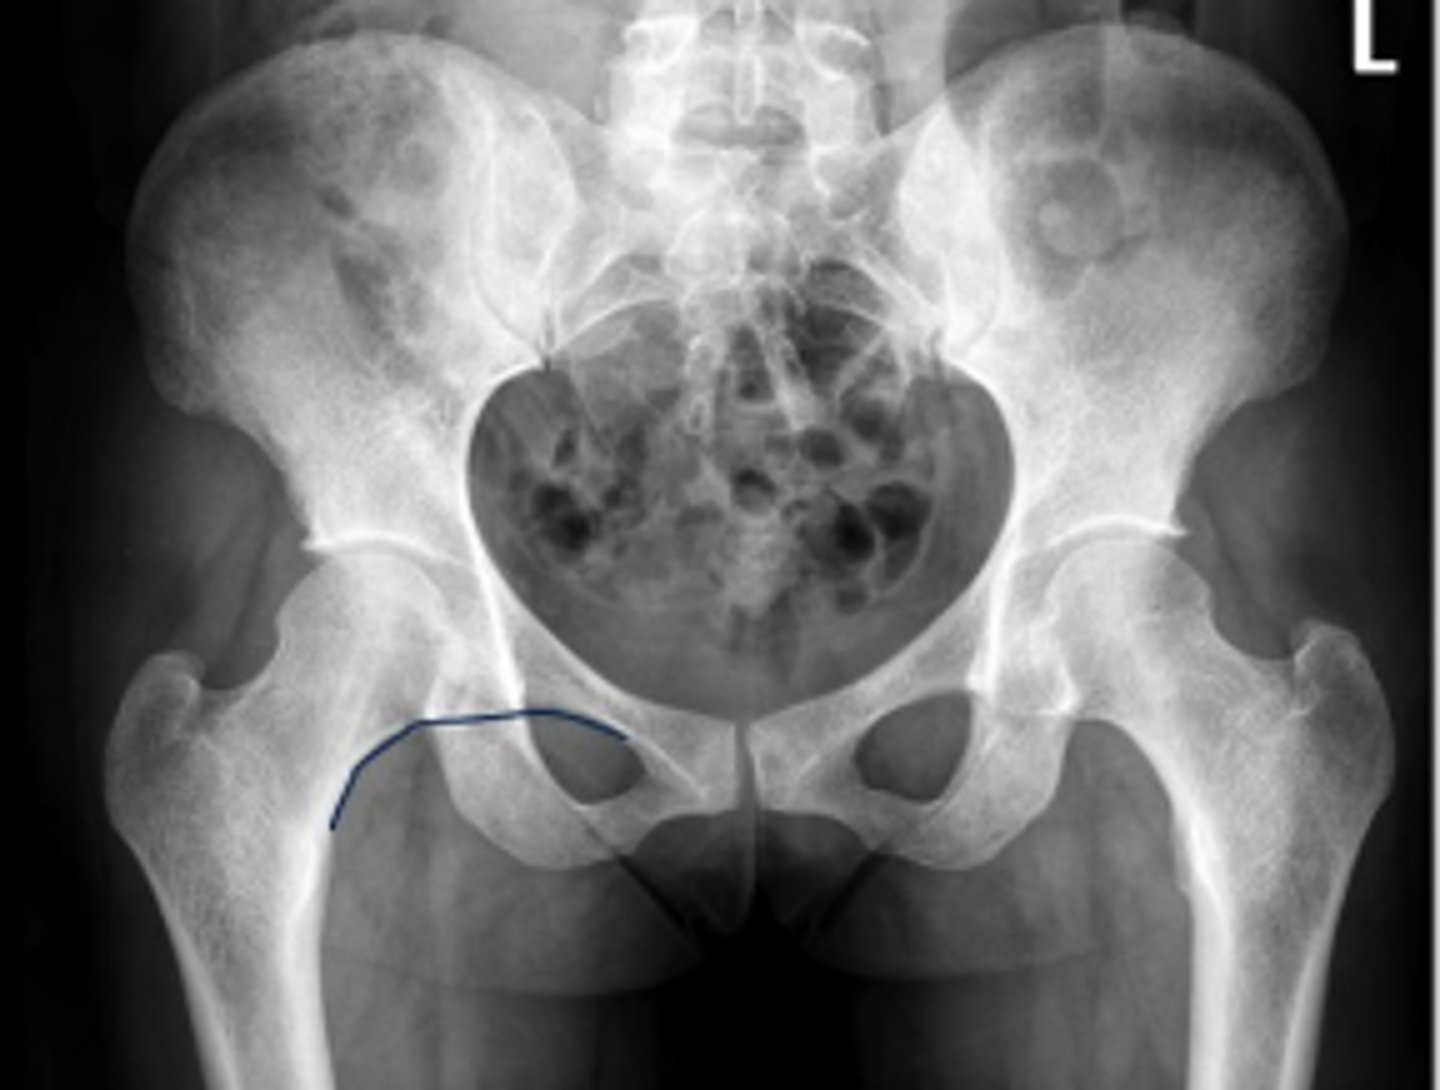

Right iliopectineal line

What is the name of the assessment?

Right ilioischial line

Center edge angle

20-40 degrees

What is the normal range for this assessment?

A vertical line is drawn upwards from the center

of the head of the femur.

The second line is drawn from the center of the femur head to the outer superior-lateral aspect of the acetabulum

What are the osseous landmarks for this assessment

No (normal measurement is 20-40 degrees)

Is the measurement within normal limits?

Acetabular dysplasia

Developmental dysplasia of the hip

Name 1 condition that may result in a measurement <20 degrees?

AP pelvis and AP hip views

Name 2 radiographic views for this assessment?

A mechanical instability of the femoroacetabular

joint characterized by a shallow acetabulum

providing insufficient covering of the femoral

head

What is developmental hip dysplasia?

AP right hip

What is the radiographic view?

Teardrop distance

6-11mm

The distance between the most medial margin of

the femoral head and the adjacent pelvic

teardrop

What are the osseous landmarks for this assessment?

Yes (normal is 6-11mm)

Femoroacetabular joint inflammation

Name 1 condition that may result in a measurement of 15mm?

Late stage degenerative joint disease

Protrusio acetabuli

Name 2 conditions that may result in a measurement of 3mm?

Waldenstrom's sign

What is the named sign if this assessment has a value > 2mm difference

between the left and right side?

Hip joint space width

Superior joint space is 3-6mm

Axial joint space is 3-7mm

Medial joint space is 4-13mm

Superior joint space-> The measurement between the most convex superior aspect of the femoral head and the adjacent acetabulum

Axial joint space -> The measurement between the

femoral head and the acetabulum lateral to the

acetabular notch

Medial Joint space -> The measurement between the most medial margin of the femoral head and the adjacent pelvic teardrop

Yes

Are the measurements within normal limits?

Degenerative joint disease

Name 1 condition that may result in a measurement of <3mm for the superior joint space?

Pubic symphysis width

3.8-6mm (average of 5mm)

What is the normal range for this assessment in women?

The distance between the articular surfaces of

the middle of the pubic symphysis

No

Post-traumatic diastasis, inflammatory resorption

Name 2 conditions that may result in a measurement of 12 mm?

AP pelvis or bilateral hips

Name the radiographic view